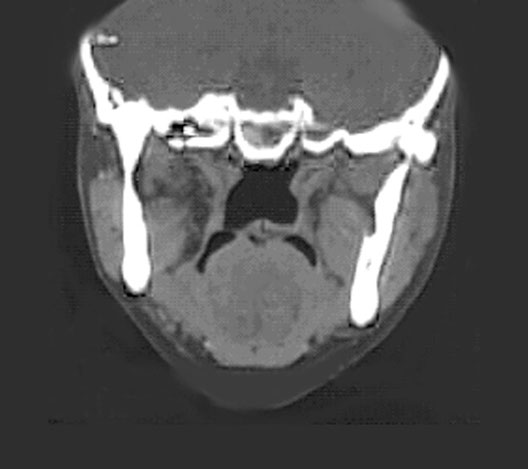

Head CT

Roll mouse over image to display labels.

1. Lateral pterygoid muscle

2. Masseter muscle

3. Medial pterygoid muscle

4. Soft palate

5. Tongue

6. Nasal cavity